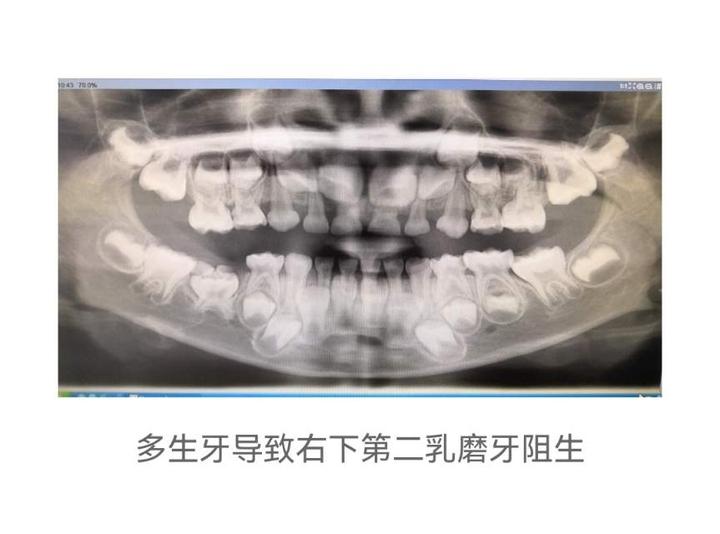

3.恒牙、乳牙阻生,不能萌出